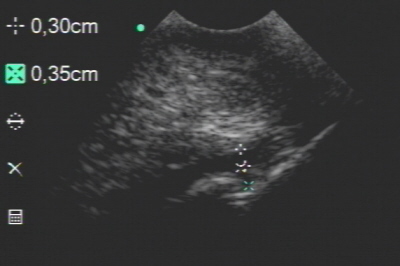

Insertionsbereich der tiefen Beugesehne und des unteren Strahlbeinbandes unauffällig